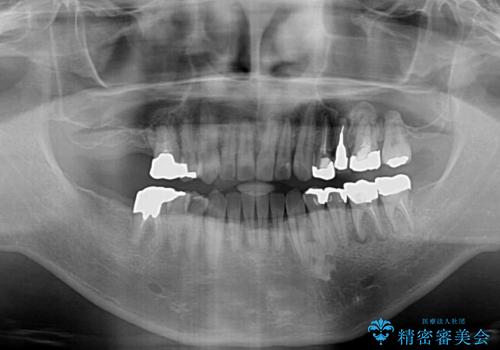

前歯の反対咬合をワイヤー矯正で改善して噛みやすく

- 咬み合わせの悪さを気にして来院された患者様です。

来院当初は、奥歯の銀歯が問題で咬み合わせが悪いと思っていらっしゃいましたが、前歯の反対咬合を改善することが最優先とご説明し、矯正治療を行うこととしました。

奥歯には抜歯が必要な歯があったため、事前に抜歯を行い、その後ワイヤー装置にて治療を開始しました。

前歯の反対咬合が改善する過程では、奥歯が咬みにくくなるため、食事では辛い思いをされていたようです。

矯正治療後は安定した咬み合わせとなり、顎の違和感がなくなったとのことでした。

今後はむし歯や銀歯を治療していく予定です。